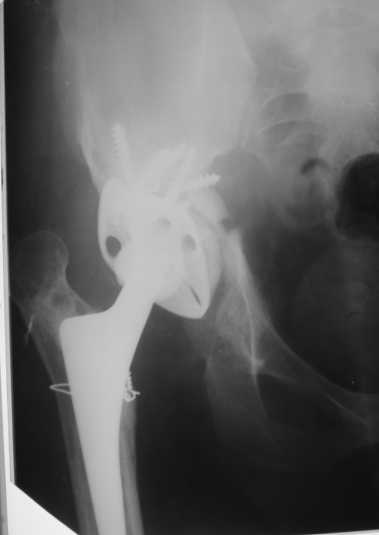

Обращение в нашу клинику в 2008 г. - демонтаж аппарата (рис. 4). Сегодня укорочение 8 см. Слева - протез стабилен, безболезнен.